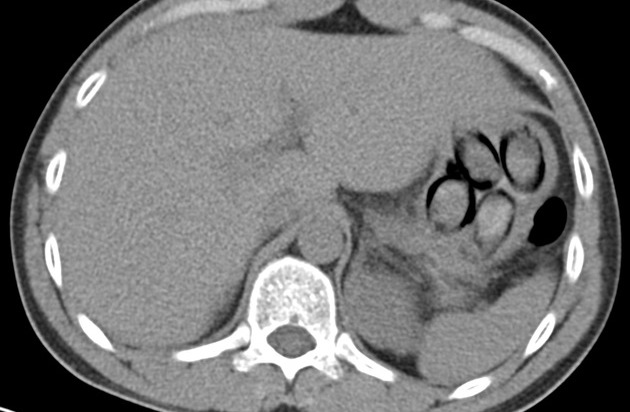

"Die Röntgenaufnahme in einem nahegelegenen Krankenhaus bestätigte letztendlich den Verdacht meiner Kolleginnen und Kollegen, denn im Magen des Mannes waren mehrere Drogenpäckchen klar zu erkennen. Insgesamt schied der Mann dann unter Überwachung sieben sogenannte Bodypacks mit insgesamt mehr als 100 Gramm Kokain aus", so Jens Ahland, Pressesprecher des Hauptzollamts Köln.